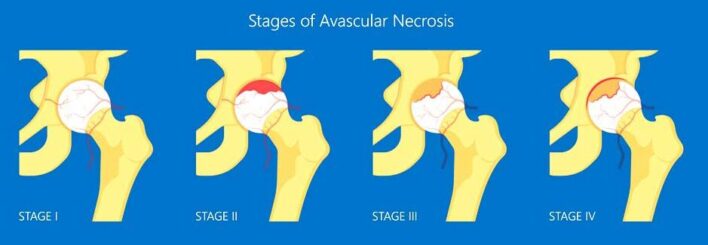

Phân giai đoạn theo Ficat

- Giai đoạn I: Không triệu chứng; xác định bằng cộng hưởng từ

- Giai đoạn II: Các thay đổi X quang;

- Xơ hoá, thiểu xương, nang dưới sụn

- Giai đoạn III: Hẹp khe khớp; Mất đường cong tròn

- Giai đoạn IV: Xẹp xương dưới sụn

Hệ thống phân giai đoạn của Steinberg gồm bảy giai đoạn:

| Giai đoạn | Các đặc điểm |

| 0 | X quang, xạ hình xương và MRI bình thường |

| I | X quang bình thường, xạ hình xương và/ hoặc chụp cộng hưởng từ bất thường |

| IA Nhẹ (ảnh hưởng dưới 15% chỏm xương đùi). IB Trung bình (ảnh hưởng từ 15% đến 30% chỏm xương đùi) IC nặng (ảnh hưởng hơn 30% chỏm xương đùi) | |

| II | Thay đổi nang và xơ cứng của chỏm xương đùi |

| IIA Nhẹ (ảnh hưởng dưới 15% chỏm xương đùi) IIB Trung bình (ảnh hưởng từ 15% đến 30% chỏm xương đùi) IIC Nặng (ảnh hưởng hơn 30% chỏm xương đùi) | |

| III | Xẹp dưới sụn (dấu hiệu lưỡi liềm) mà không làm dẹt chỏm xương đùi |

| IIIA Nhẹ (ảnh hưởng dưới 15% chỏm xương đùi) IIIB Trung bình (ảnh hưởng từ 15% đến 30% chỏm xương đùi) IIIC Nặng (ảnh hưởng đến hơn 30% chỏm xương đùi) | |

| IV | Dẹt chỏm xương đùi/ xẹp chỏm xương đùi |

| IVA Nhẹ (ảnh hưởng dưới 15% chỏm xương đùi) IVB Trung bình (ảnh hưởng từ 15% đến 30% chỏm xương đùi) IVC Nặng (ảnh hưởng hơn 30% chỏm xương đùi) | |

| V | Hẹp khe khớp và/hoặc các thay đổi ổ cối |

| VA nhẹ VB Trung bình VC Nặng | |

| VI | Bệnh khớp thoái hóa tiến triển |